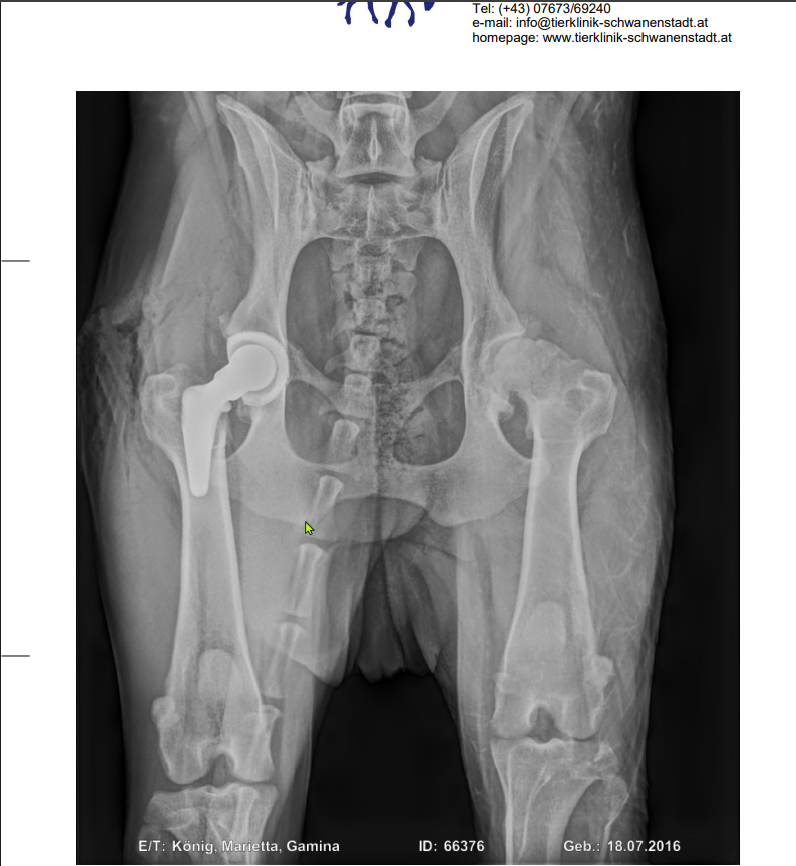

Nach einer ausführlichen Untersuchung wurde dann ein Röntgen gemacht bei dem sich zeigte, dass beide Hüften unserer Maus komplett zerstört sind und sie beidseitig ein neues Hüftgelenk braucht.

Bei den Bildern findet ihr den Kostenvoranschlag für eine der beiden benötigten Operationen und das aktuelle Röntgenbild.

After a thorough examination, an x-ray was taken, which revealed that both of our little girl's hips were completely destroyed and she needed a hip replacement on both sides.

In the pictures you will find the cost estimate for one of the two required surgeries.